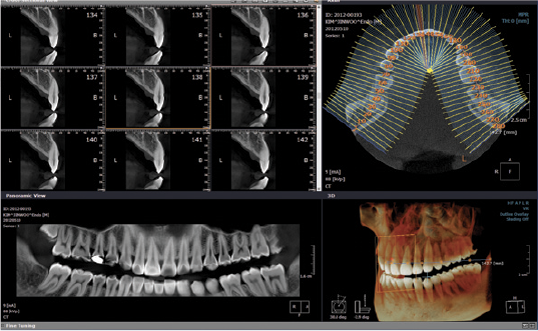

- Studio anomalie della dentizione (anomalie di posizione dei denti del giudizio o dei canini)

- Studio di aree di sclerosi e disomogeneità ossea dei mascellari

- Studio in 3D delle articolazioni temporo-mandibolari